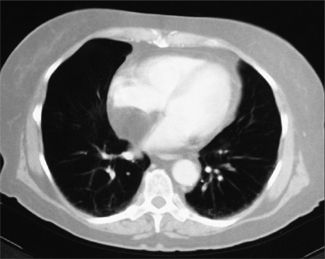

An obese 56-year-old woman was hospitalized after 2 days of chest pain, dyspnea, and palpitations. Physical examination revealed no abnormalities, and serial cardiac enzyme studies and an ECG ruled out myocardial infarction. Suspicion was aroused, however, when transesophageal echocardiography showed a lesion in the mediastinum.

A CT scan of the chest revealed a mass in the mediastinum, and the diagnosis of mediastinal lipomatosis was confirmed by the tumor's characteristic low density (from 220 H to 2100 H). The patient's chest pain subsided without any intervention. Two years later, the mass showed no change in size, confirming a benign process.

Lipomatosis is often associated with obesity, corticosteroid treatment, or Cushing disease. In most cases, the lesions are benign, although liposarcomas do occur in the mediastinum.